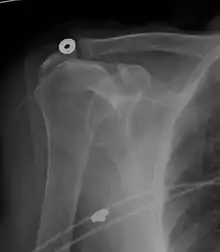

Diagnostic modalities, dependent on circumstances, include X-ray, MRI, MR arthrography, double-contrast arthrography, and ultrasound. Although MR arthrography is currently considered the gold standard, ultrasound may be most cost-effective.[35] Usually, a tear will be undetected by X-ray, although bone spurs, which can impinge upon the rotator cuff tendons, may be visible.[36] Such spurs suggest chronic severe rotator cuff disease. Double-contrast arthrography involves injecting contrast dye into the shoulder joint to detect leakage out of the injured rotator cuff,[37] and its value is influenced by the experience of the operator. The most common diagnostic tool is magnetic resonance imaging (MRI), which can sometimes indicate the size of the tear, as well as its location within the tendon. Furthermore, MRI enables the detection or exclusion of complete rotator cuff tears with reasonable accuracy and is also suitable for diagnosing other pathologies of the shoulder joint.[38]